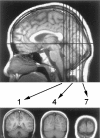

Twelve normal subjects viewed alternating sequences of unfamiliar faces, unpronounceable nonword letterstrings, and textures while echoplanar functional magnetic resonance images were acquired in seven slices extending from the posterior margin of the splenium to near the occipital pole. These stimuli were chosen to elicit initial category-specific processing in extrastriate cortex while minimizing semantic processing. Overall, faces evoked more activation than did letterstrings. Comparing hemispheres, faces evoked greater activation in the right than the left hemisphere, whereas letterstrings evoked greater activation in the left than the right hemisphere. Faces primarily activated the fusiform gyrus bilaterally, and also activated the right occipitotemporal and inferior occipital sulci and a region of lateral cortex centered in the middle temporal gyrus. Letterstrings primarily activated the left occipitotemporal and inferior occipital sulci. Textures primarily activated portions of the collateral sulcus. In the left hemisphere, 9 of the 12 subjects showed a characteristic pattern in which faces activated a discrete region of the lateral fusiform gyrus, whereas letterstrings activated a nearby region of cortex within the occipitotemporal and inferior occipital sulci. These results suggest that different regions of ventral extrastriate cortex are specialized for processing the perceptual features of faces and letterstrings, and that these regions are intermediate between earlier processing in striate and peristriate cortex, and later lexical, semantic, and associative processing in downstream cortical regions.